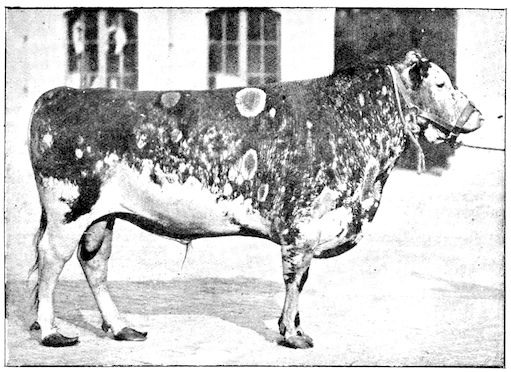

Fig. 6.—Osseous cachexia. This condition developed in two months, the last month of gestation and the first of lactation.

14Course. The development of the disease is slow, lasting from one to three months as a rule, and is little influenced by hygienic conditions. Good milking cows, however, seem to be most frequently attacked, probably because of the great losses of nutritive material which occur through the milk. The calves borne by such animals are often rachitic. Oxen are less commonly attacked. Horses rarely suffer from the disease in France, but frequently in Tonquin. Pigs reared on very poor soil seldom escape attack.

The disease has been observed in England, Scotland, United States, France, Belgium, and Jutland, and generally in districts with low-lying damp pastures. It attacks cows which are heavy milkers. Susceptibility appears to increase with advancing age.

Symptoms. The first symptoms are difficult to detect and interpret, especially at the commencement of an outbreak and in parts where the disease is rare they may lead to confusion and errors in diagnosis. On the other hand, in regions where the disease is common the practitioner will be able to form his diagnosis from the appearance of the first signs.

To render clear the mode in which the symptoms develop we may divide the progress of the disease into four phases, though this grouping is somewhat arbitrary.

91. The initial phase is not well marked, and is announced by digestive disturbance and by wasting. The former of these symptoms may be referred to some other cause, but consists in irregularity, diminution and sometimes perversion of the appetite. These earlier signs are soon followed by loss of spirits, and some interference with movement, but the symptoms only become of importance or attain their full development when the animals remain lying for a long period in the stable.

2. The second phase is characterised by more precise signs, which become almost pathognomonic. Difficulty in rising is added to the already existing tendency to remain lying, and to the interference with movement.

When lying down the patient no longer responds to the trifling stimulus, which a healthy animal needs to cause it to rise. It remains languid and apparently lazy, though in reality it experiences pain and difficulty on attempting to get up. The least muscular effort when lying down often causes it to moan, as do efforts to change its position or to walk. Even when standing still, it may appear to be in pain, and patients often assume a position similar to that of a horse suffering from laminitis.

At the end of this second phase, swellings appear, due to synovitis or arthritis of the extremities, synovitis of the sesamoid or navicular sheaths or to inter-phalangeal arthritis or arthritis of the fetlock joint. Weakness becomes marked, and the appetite is very irregular.

10Secretion of milk diminishes or ceases and abortion is not uncommon.

3. The third phase is characterised by fractures, and it is this peculiarity of the disease which has procured for it the names of fragilitas ossium, and osteoclastia. These fractures may affect any portion of the skeleton. Animals so suffering sometimes break a leg whilst trotting or the pelvis in simply jumping over a ditch; a collision with a fixed object like the jamb of the stable door, or a fall on the ground, may result in the fracture of one or several ribs.

Fig. 3.—Pig suffering from osseous cachexia (fourth stage).

Such shocks would be of no importance to a healthy animal, but to one suffering from osseous cachexia, any violence, or even the slightest muscular effort may be followed by fracture of the gravest character, involving even the vertebral column. In cows the pelvis, femur, and tibia are most frequently injured.

In horses, particularly in riding horses, fractures are commonest in the region of the forearm, cannon bone, and anterior phalanges. So extremely fragile are the bones at this stage that the horse represented herewith broke twelve ribs at one time by simply falling on its side. It is interesting to note that such fractures are never accompanied by any extensive bleeding. They have little tendency to repair, no real callus formation occurs, and on post-mortem examination one often finds the ends unconnected by temporary callus, worn, and rounded by reciprocal friction.

At this stage but under other circumstances, the animals show great reluctance to rise, remaining down for twelve to twenty-four hours without shifting their position. If forced to get up, they stand as though fixed in one position, the respiration and circulation become rapid, and they soon grow tired and fall.

114. The fourth phase, or period of osteomalacia, i.e. softening of the bones, is also the last. It is rarely seen in large animals like horses and oxen, because accidents so often accompany the preceding stages and necessitate slaughter; but it is common in goats and pigs.

In this phase the bones become elastic, soft and depressible, yielding to the pressure of the operator’s fingers.

Fig. 4.—Deformity of the face in the horse shown in Fig. 2.

The flat bones are particularly liable to this change, which is common to domesticated animals. The bones of the head are the first to suffer; later those of the pelvis. The lower jaw becomes swollen, particularly about the centre of the branches which may attain three, four, or five times, their normal thickness.

The depression in the submaxillary space disappears. The upper jaw undergoes similar changes, becoming deformed and thickened until the cavities of the sinuses and the hollow appearance of the palate are lost, while the face is so changed that it cannot be recognised as that of a horse, goat, etc.

The molar teeth are almost buried, their tables alone being visible at the bottom of a depression, the edges of which rise above the neighbouring parts (pig).

Mastication is clearly impossible, the jaws appear paralysed, the muscles powerless, and only swallowing is possible, a fact which explains why life is only prolonged to this stage in animals which can be fed with a spoon or bottle (pigs and goats). The bones of the cranium, although greatly changed in texture, are always less deformed than those of the face.

The changes are such that it is often easy with a mere post-mortem knife to cut the head completely in two. Osseous tissue, properly so-called, has disappeared.

All the constituent tissues, with the exception of the skin and muscles, i.e., the bone, periosteum and aponeuroses, have the appearance and consistence on section of the fibro-lardaceous tissue seen in chronic inflammation.